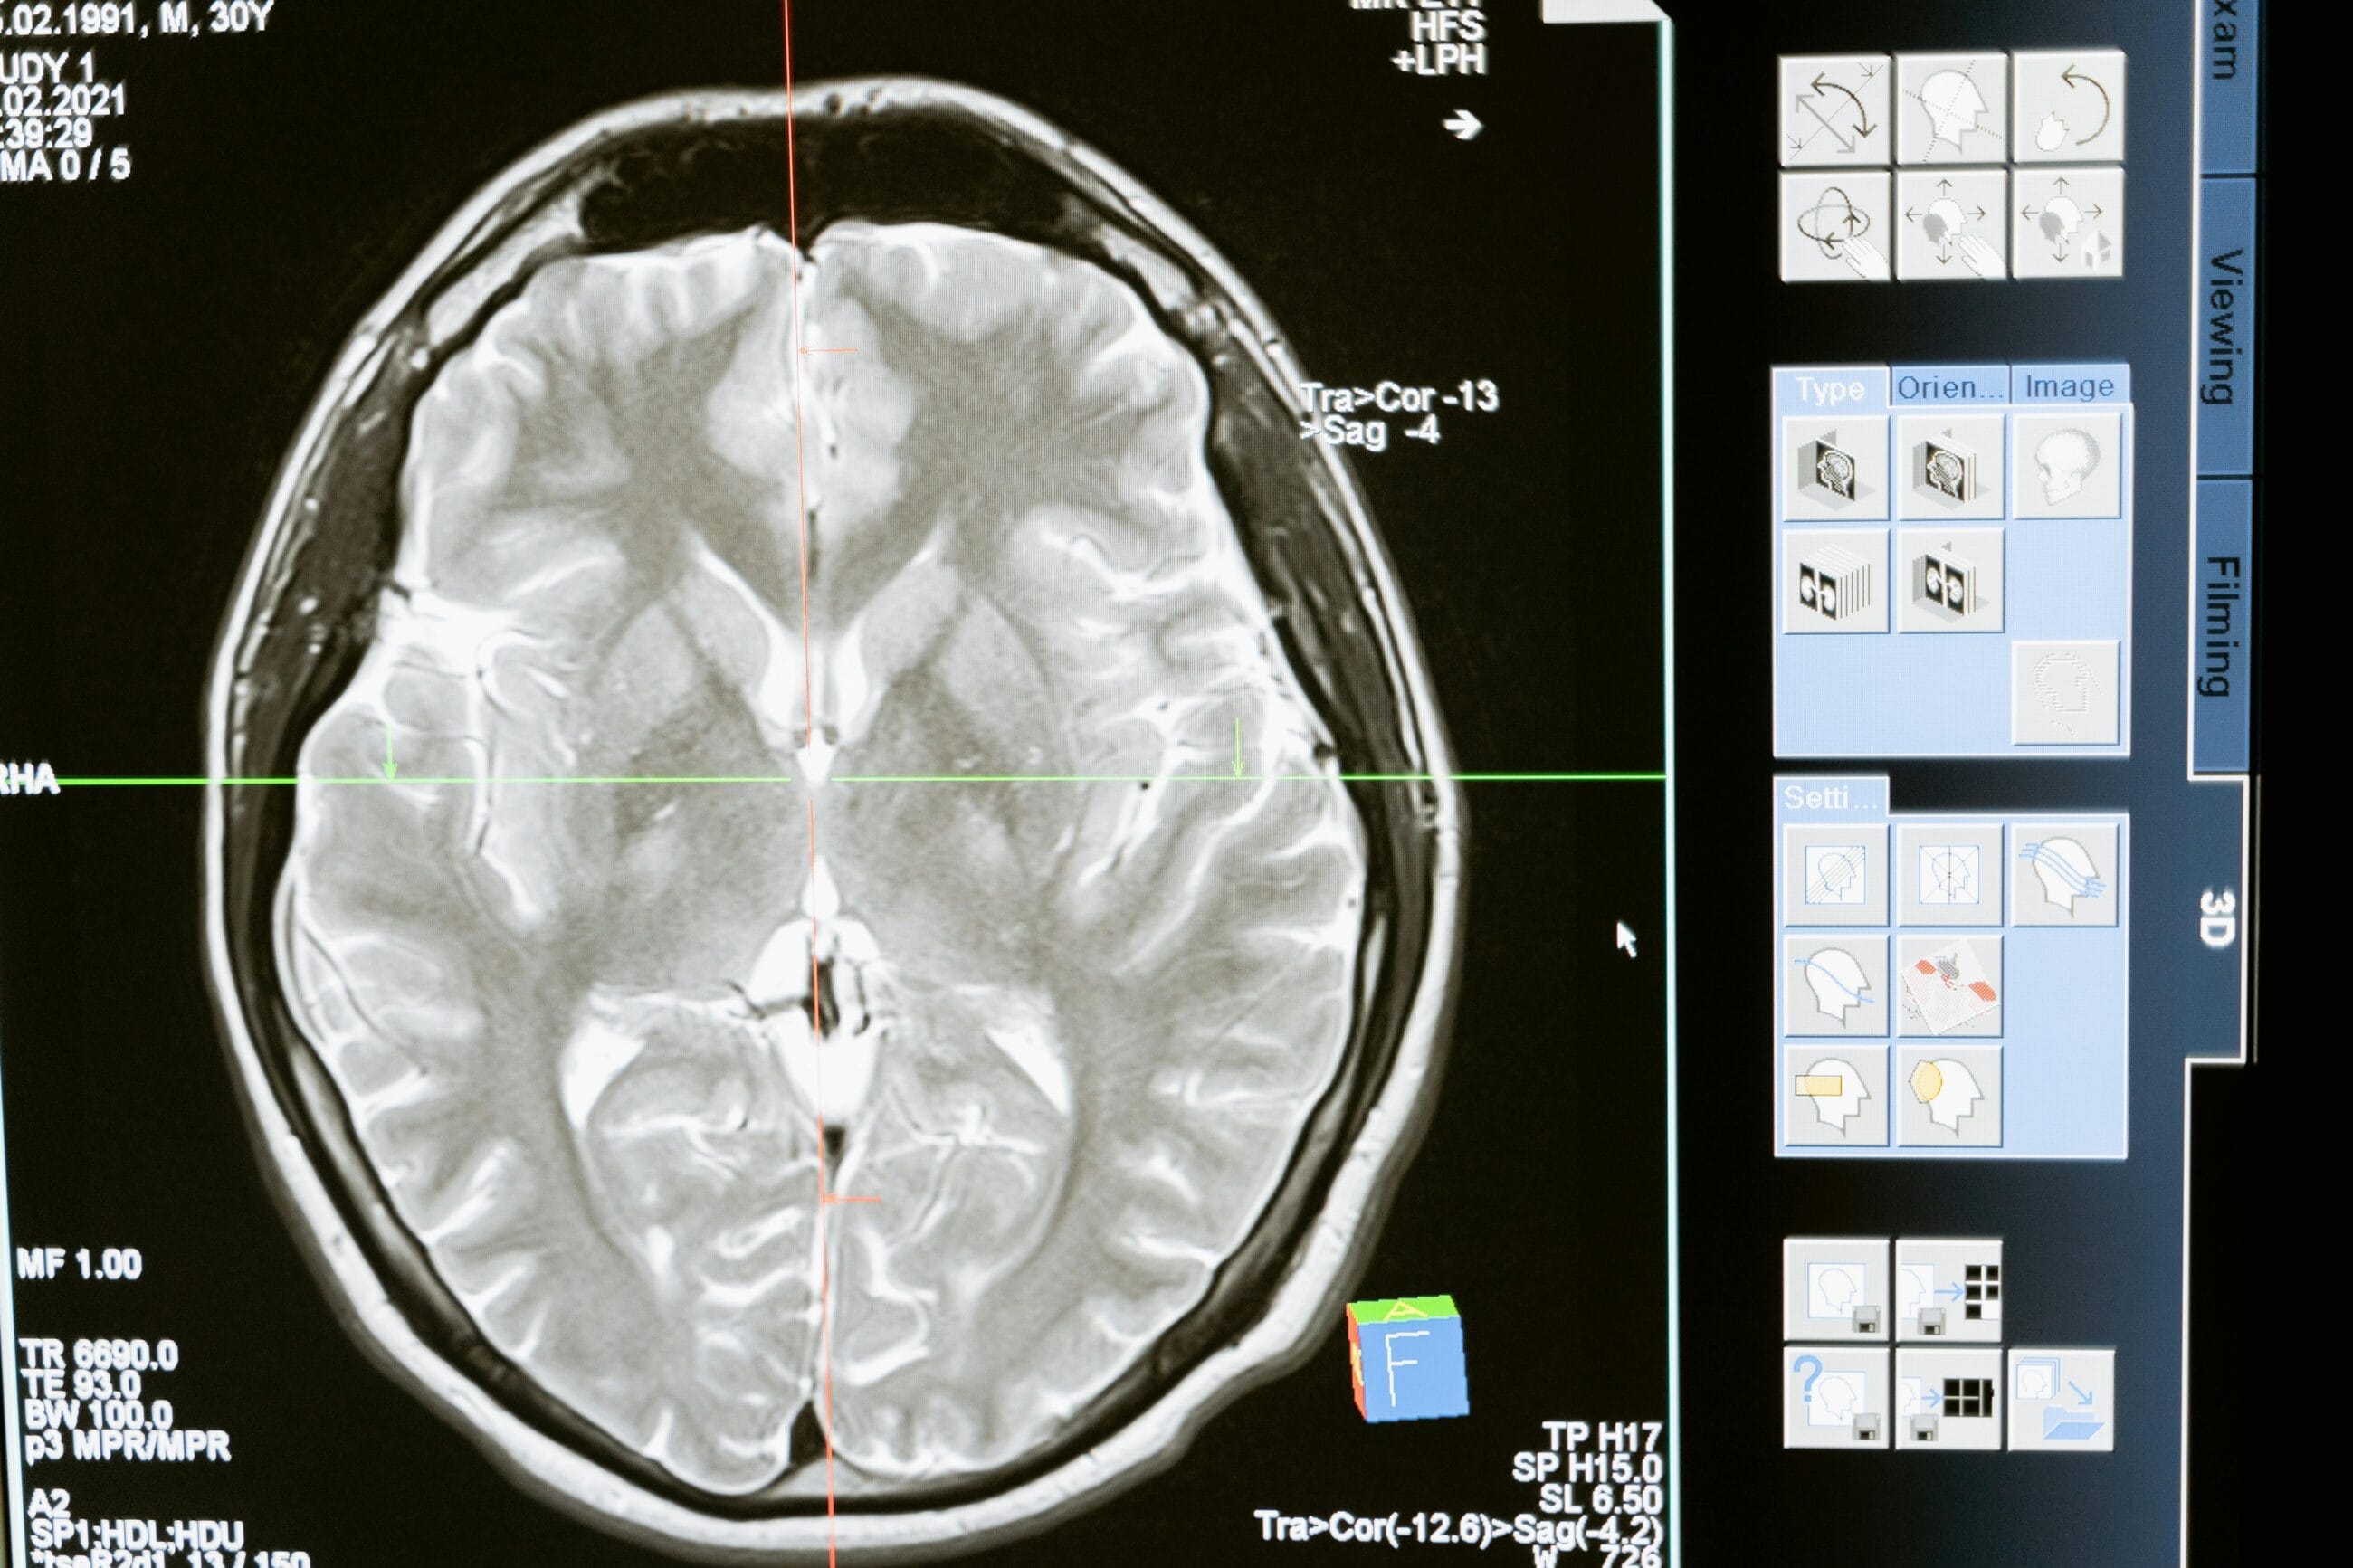

PET scans are groundbreaking tools in modern medicine. Simply put, they are imaging tests that help visualize the metabolic and functional activity of tissues and organs within the body. Unlike X-rays, CT (computed tomography) scans, or other imaging methods, PET imaging reveals how your tissues are functioning at a molecular level.

- Gamma ray detection is performed by the PET scanner, which constructs detailed images showing areas of high and low metabolic activity, often combined with CT images for more accurate results.

It’s a non-invasive outpatient procedure that takes about 30 minutes and helps doctors help diagnose various conditions. For example, cancer cells, which have high metabolic rates, absorb more tracer and appear as bright spots on the scan.